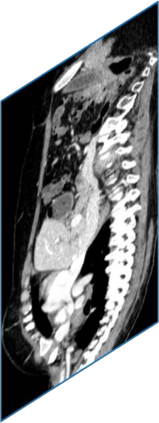

Due to the constraints of the imaging device and high cost in operation time, computer tomography (CT) scans are usually acquired with low intra-slice resolution. Improving the intra-slice resolution is beneficial to the disease diagnosis for both human experts and computer-aided systems. To this end, this paper builds a novel medical slice synthesis to increase the between-slice resolution. Considering that the ground-truth intermediate medical slices are always absent in clinical practice, we introduce the incremental cross-view mutual distillation strategy to accomplish this task in the self-supervised learning manner. Specifically, we model this problem from three different views: slice-wise interpolation from axial view and pixel-wise interpolation from coronal and sagittal views. Under this circumstance, the models learned from different views can distill valuable knowledge to guide the learning processes of each other. We can repeat this process to make the models synthesize intermediate slice data with increasing inter-slice resolution. To demonstrate the effectiveness of the proposed approach, we conduct comprehensive experiments on a large-scale CT dataset. Quantitative and qualitative comparison results show that our method outperforms state-of-the-art algorithms by clear margins.